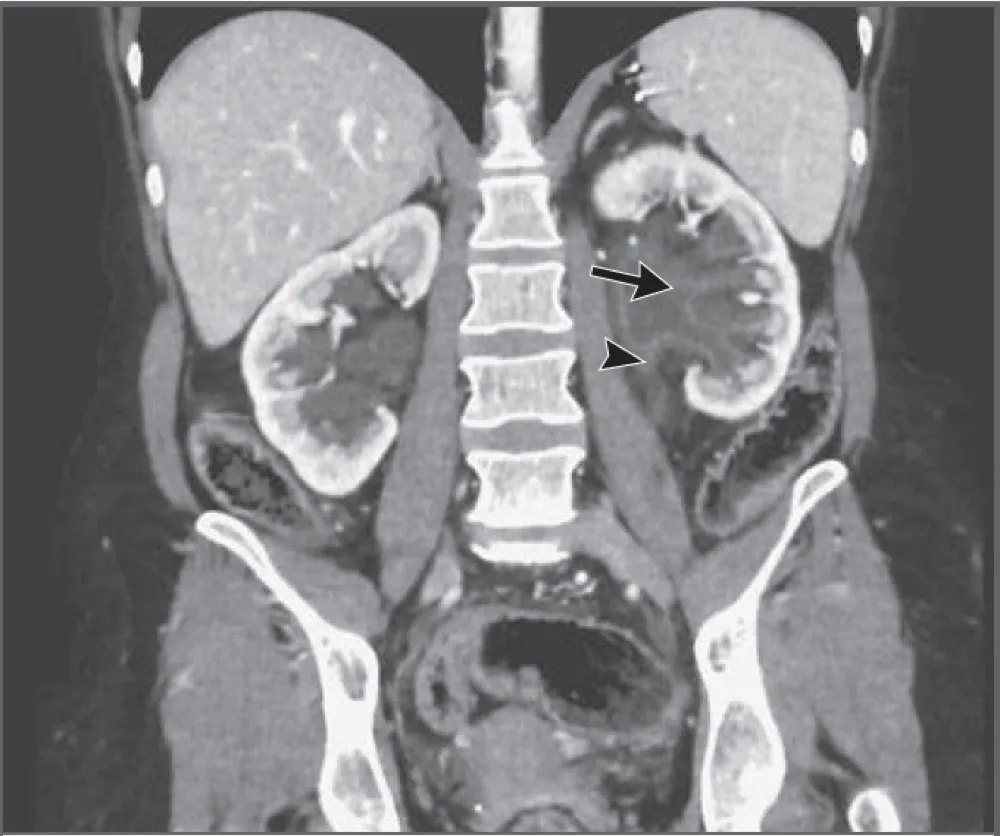

IRA + Icterícia: Um Caso que Exige Investigação Detalhada